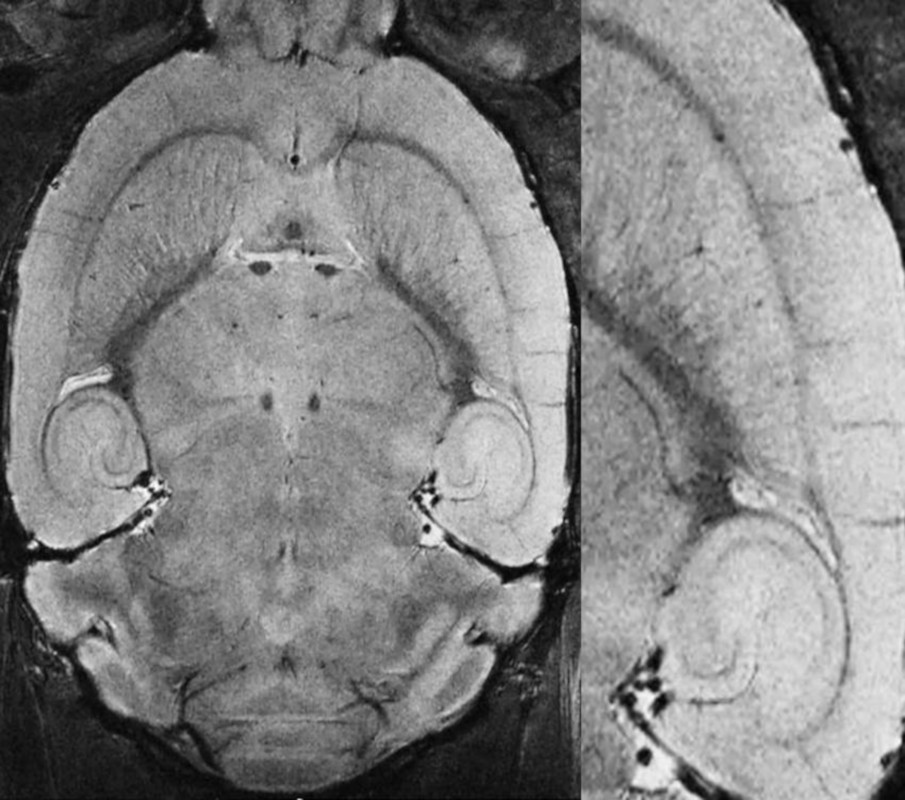

超高分辨率,高对比度T2加权活体小鼠大脑数据获得15.2特斯拉MRI CryoProbe。方法:RARE,分辨率:(29 x 29)µm2,切片厚度:203µm,切片:12,扫描时间:26分钟。

活体小鼠大脑,分辨率为29µm,用MRI CryoProbe在15.2 T下测量。采集细节:RARE,分辨率:(29 × 29 × 200)µm³,TR: 3.5 s, TE: 25 ms,回波:6,切片:7

在临床前MRI中,低温冷却MRI CryoProbes[2]提供了额外的灵敏度提升[3],并已被广泛使用。结合超高频MRI,额外的增益是显著的,并在合理的测量时间[4]实现最高质量的图像。因此,例如,可以在配备MRI CryoProbe的临床前15.2特斯拉上轻松获得超高分辨率的体内小鼠大脑数据。